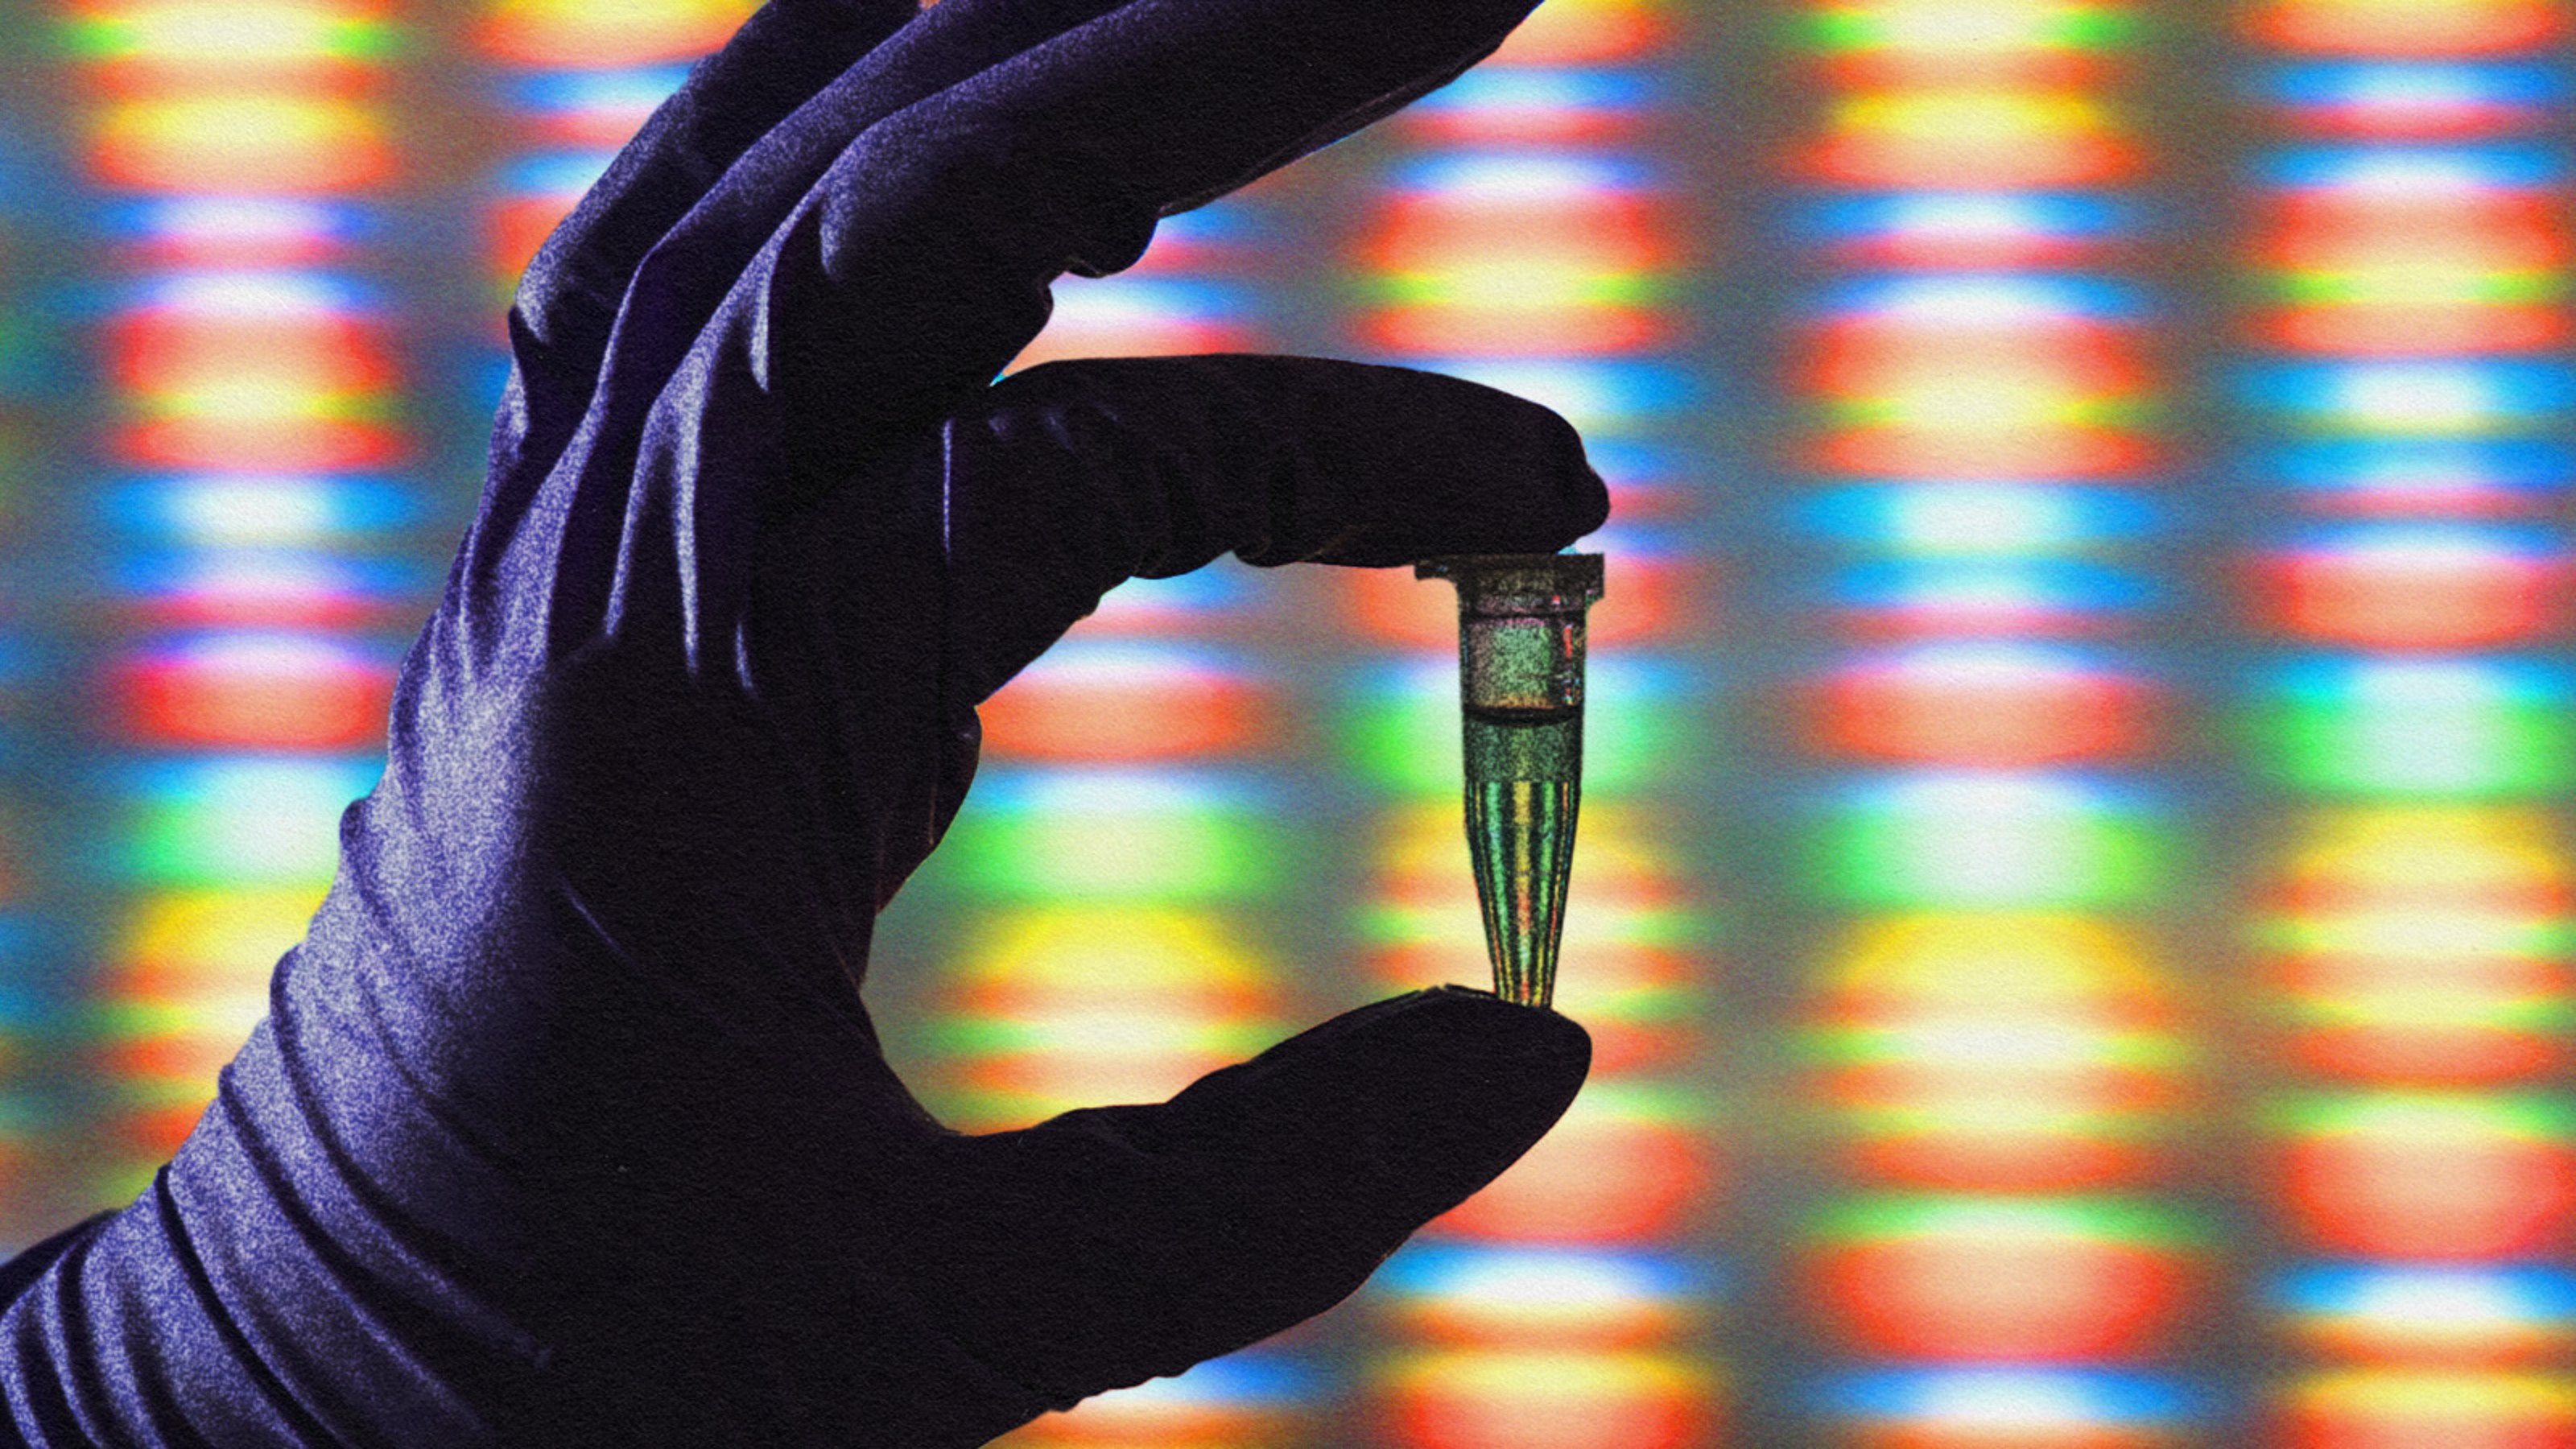

“The promise of the Human Genome Project has finally arrived.”

Cancers can’t develop without genetic mutations — or can they?

Vaccines targeting some of our deadliest cancers are showing promise in early trials.

They call it “Judo T-cell therapy,” and it’s 100 times more potent than regular CAR-T cells.